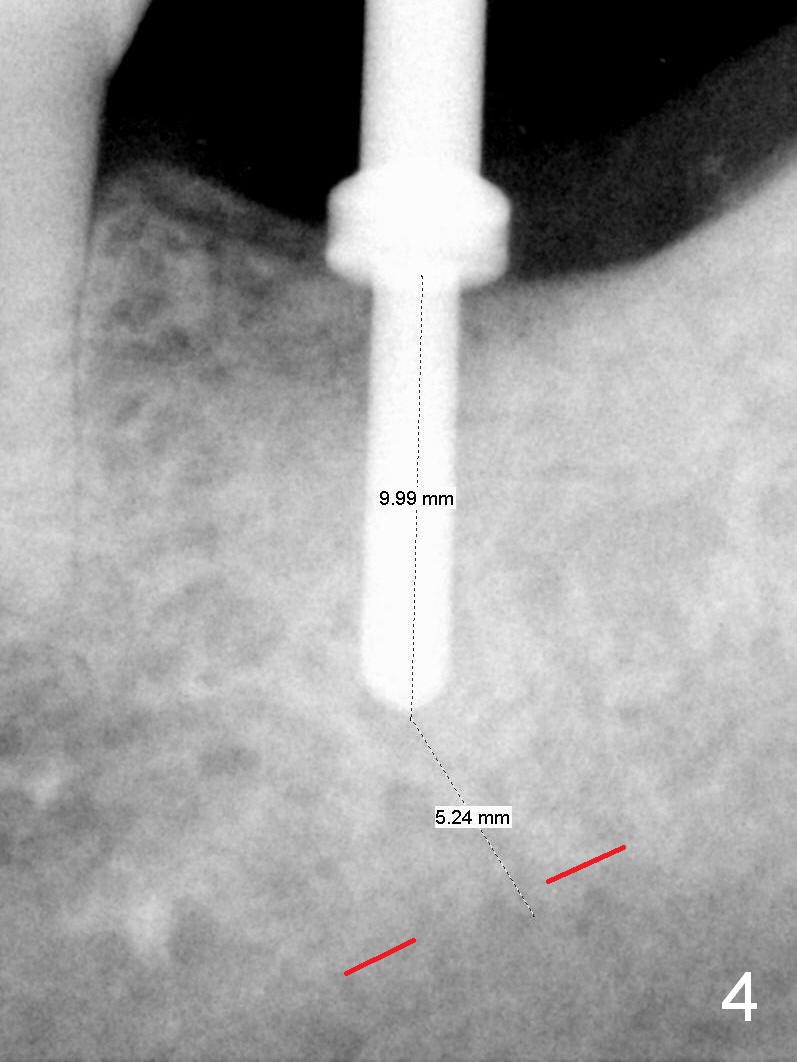

A 48-year-old lady is a dental phobic, requesting extraction of the lower left 2nd molar (Fig.1). She returns for implant placement 9 months post extraction (Fig.2). The ridge is mildly to moderately atrophic. It appears that a 5x12 mm implant is appropriate for the site (Fig.3). For safety, osteotomy is initiated at the depth of 10 mm; it appears that there is enough height for a 12 mm implant (Fig.4). The depth is controlled by drill stopper (Fig.5 S). Finally a 5x12 mm implant is apparently safely placed (Fig.6). A healing abutment is placed and the incision is sutured with 4-0 Chromic gut (Fig.7). Perio dressing is applied around the healing abutment for wound protection (Fig.8). It appears that the healing abutment (Fig.8': *) helps stabilize the perio dressing, which remains in place 1 week postop. When the perio dressing is removed, the wound around the healing abutment is healing (Fig.9). There is no bone loss around the implant 3 months postop (Fig.10 (H: healing abutment), or 16 months postop (i.e., 9 months post cementation, Fig.11,12). The patient complains of pain when she chews with the implant crown, but pain stops whenever she does not bite. Percussion does not elicit any discomfort. The gingiva is healthy. There is possibility of the buccal plate being thin or the lingual plate being perforated in the submandibular fossa. If the discomfort remains the same next 6 months, CBCT will be prescribed.